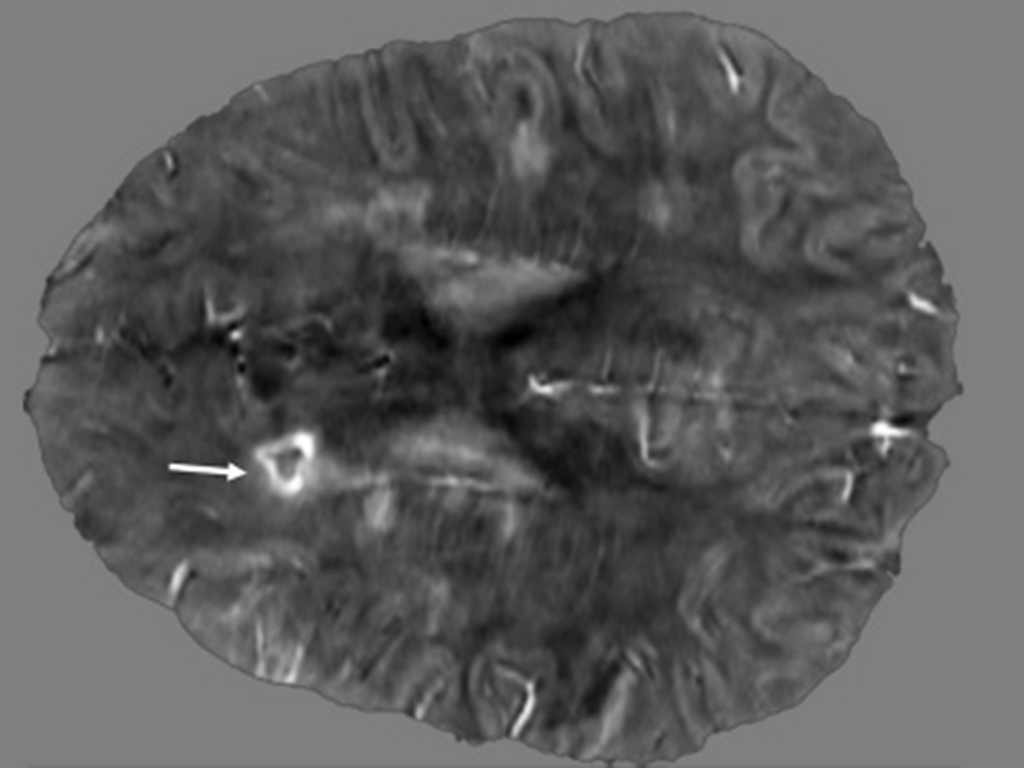

MRI brain image from an MS patient

This image of the brain of a 45-year-old female with secondary-progressive MS indicates with a white arrow the presence of a paramagnetic rim lesion. The image was obtained using Quantitative Susceptibility Mapping (QSM), an advanced MRI technique that can detect these lesions.